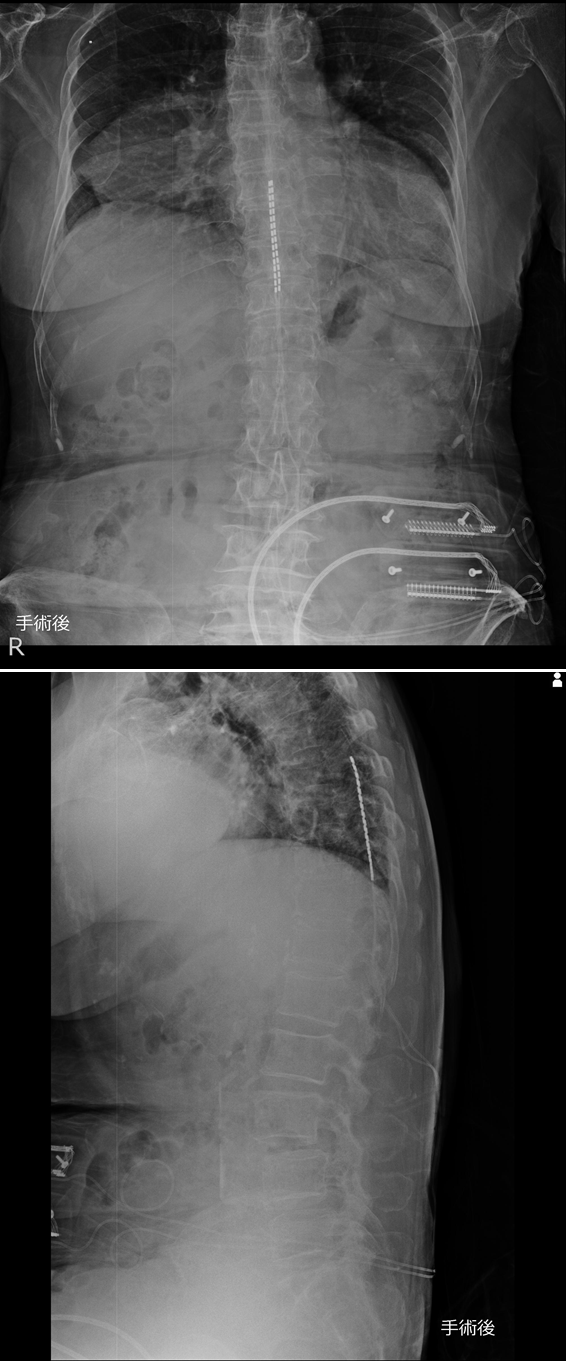

85-year-old woman, Chief complaint: Low back pain, lower limb pain, Current medical history: She was diagnosed with lumbar spinal canal stenosis by an orthopedic surgeon at a nearby clinic and was treated with oral medication Figure 1. She had low back and leg pain, and intermittent claudication with bilateral low back pain and heaviness in the lower extremities after walking 50 m and unable to walk without rest. A spinal cord stimulation therapy trial (Boston Scientific) was performed at our hospital. In this trial, Fast-Acting Sub-Perception (FAST) stimulation was performed postoperatively, and she was able to walk more than 200 m the day after surgery with FAST stimulation alone, and the Numerical Rating Scale (NRS) improved from 10 to 2, and it was 0 after the trial at an outpatient visit one month later. The average walking time (in seconds) when walking 210 cm improved from 4.98 to 3.13 seconds. Satisfaction was rated on a 5-point scale, she was 5, very satisfied. Sleep quality (on a scale of 10) improved from 6 to 9. Back bending improved from 27 to 54 degrees. She was able to run after the trial. Three months have passed since the trial and her progress is good.

Figure 1 X-ray frontal and lateral views after spinal cord stimulation therapy trial.